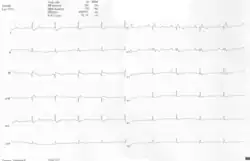

ECG 12-derivações de uma mulher com anomalia Ebstein. O ECG mostra sinais de dilatação do átrio direito, melhor observado na derivação V1. Outros sinais observáveis são as ondas P alargadas e apiculadas. Também existe um padrão de bloqueio de ramo direito e um bloqueio AV de 1ograu (intervalo PR-prolongado) devido ao atraso de condução intra-atrial. Não há evidência de um feixe de Kent nesse paciente. Existe inversão de onda T em V1-4 e uma onda Q proeminente em D3; essas alterações são características na anomalia de Ebstein e não refletem alterações isquêmicas nesse paciente.

Outras anormalidades que podem ser vistas no ECG incluem (1) sinais de dilatação do átrio direito, ou ondas P espiculadas e alargadas(ondas P 'Himalayan'); (2) Bloqueio atrioventricular de primeiro grau que se manifesta como um intervalo P-R prolongado; (3) complexos QRS de baixa amplitude nas derivações precordiais direitas; (4) bloqueio do ramo direito atípico; (5) inversão de onda T em V1-V4 e ondas Q em V1-V4 e D2, D3 e aVF.[5]